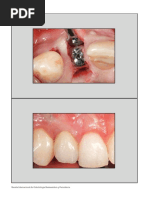

PROTOCOLO QUIRURGICO

 Procedimiento realizados bajo anestesia

local

 Por un cirujano experimentado que no

participo en la planificación digital

 Se utilizaron implantes Strauman a nivel

de hueso, diámetro de 3,3- 4,8 mm,

longitud 8-12mm

 En todas las cirugías se realizo colgajo

mucoperióstico a espesor total

Después de colocar el

implante se midió

análisis de frecuencia de

resonancia (RFA)

Medido como el cociente

de estabilidad del

implante

El torque de inserción y

se coloco un pilar de

cicatrización, para la

cicatrización

transmucosa